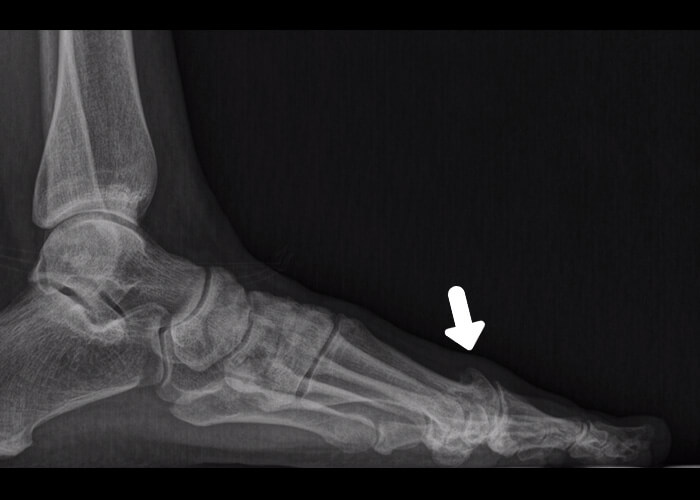

Antes y después

Te mostramos algunos ejemplos de antes y después de resolución de hallux rigidus con cirugía mínimamente invasiva del pie.